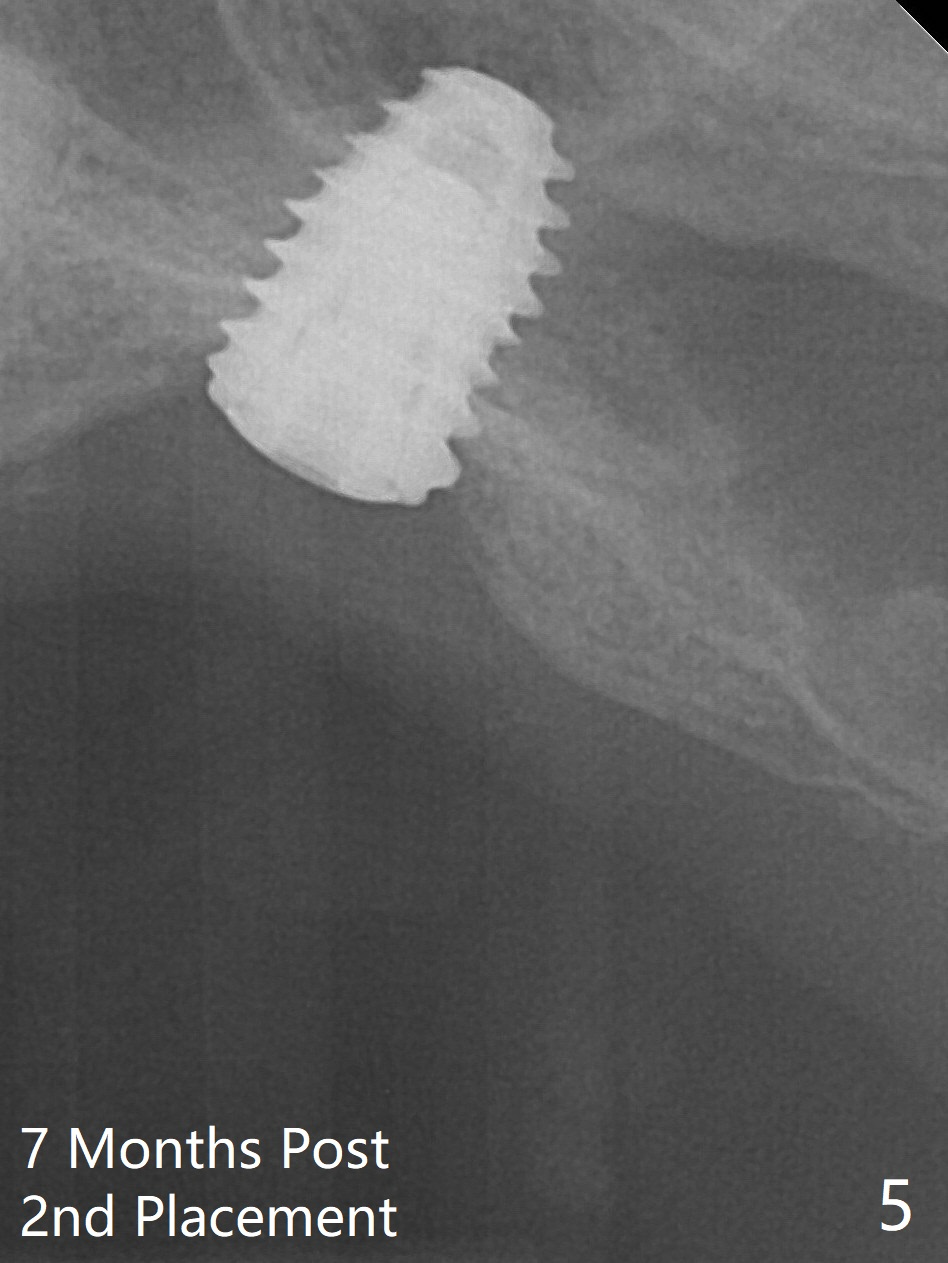

With placement of Osteogen plug (presumably for repair of the perforation) and limited amount of Vanilla at the osteotomy, a 5x7.3 mm IS implant with SLA surface treatment is placed (Fig.2, ~ 40 Ncm). When the implant is further seated (Fig.3 arrow with bone graft coronally *)), its trajectory is within the normal limit (Fig.4 blue line). If the implant fails again, it must be due to the mild sinus infection. Bone graft should have been done first. Mild tenderness exists with use of Water Pik 7 months post 2nd placement (Fig.5). Uncover shows that the implant is stable. A 6x3 mm healing abutment is placed. Next appointment a temporary crown will be fabricated for progressive loading.